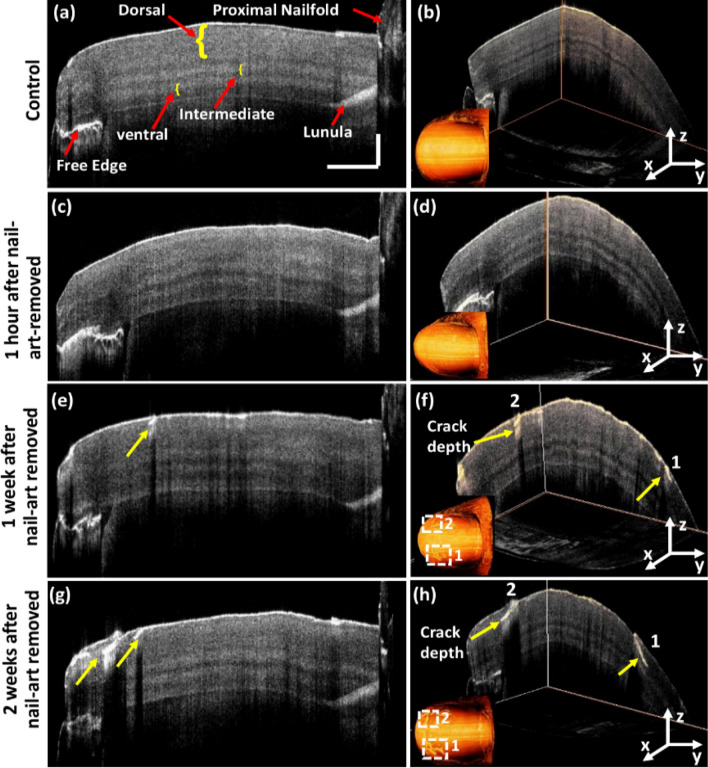

Figure 4a shows the 2D cross-sectional OCT image of the right-hand control thumbnail. Distinguishable nail plate sublayers and some other parts of the nail, such as proximal nail fold, lunula, and nail-free edge can be identified in Fig. 4a. Nail plate can be split into three sublayers: dorsal, intermediate, and ventral54,55 are marked using yellow curly brackets in Fig. 4a. OCT images can visualize lunula because of the increased back-scattering of light from this area. Figure 4b shows the 3D image of the same control thumbnail and its 3D-enface image. The 3D image and the corresponding 3D-enface images of control thumbnail were found without any crack. The 2D-OCT image of the right-hand thumbnail after 1 h of nail-art removal and the 3D-enface of the same thumbnail shown in Fig. 4c,d, respectively. 2D-OCT and 3D-enface images of thumbnail after 1 h of nail-art removal can be identified without any cracks on the nail plate, which has a similar appearance to the control 2D-OCT and 3D-enface OCT images. After 1 week of nail-art removal, both the 2D-OCT and 3D-enface OCT images can be identified with small nail cracks on the nail plate surface (indicated by yellow arrows), shown in Fig. 4e,f respectively. The progression of nail crack on the nail plate surface can be detected in both the 2D-OCT and 3D-enface OCT images after 2 weeks of nail-art removal (indicated by yellow arrows), shown in Fig. 4g,h respectively. The crack positions in 3D and three dimensional enface OCT images are marked by 1 and 2 in Fig. 4f,h.

Figure 4.

Crack detection on the right-hand thumbnail plate in 2D-OCT and their 3D-enface images at different monitoring periods. Image (a) 2D-OCT image of control thumbnail. Image (b) 3D-enface of control thumbnail. Image (c) 2D-OCT image of right-hand thumbnail after 1 h of nail-art removed. Image (d) 3D-enface of the same thumbnail after 1 h of nail-art removed. Image (e) 2D-OCT image of right-hand thumbnail after 1 week of nail-art removed. Image (f) 3D-enface of the same thumbnail after 1 week of nail-art removed. Image (g) 2D-OCT image of right-hand thumbnail after 2 weeks of nail-art removed. Image (h) 3D-enface of the same thumbnail after 2 weeks of nail-art removed. The values of horizontal and vertical scale bars are 2 mm and 0.5 mm, respectively.